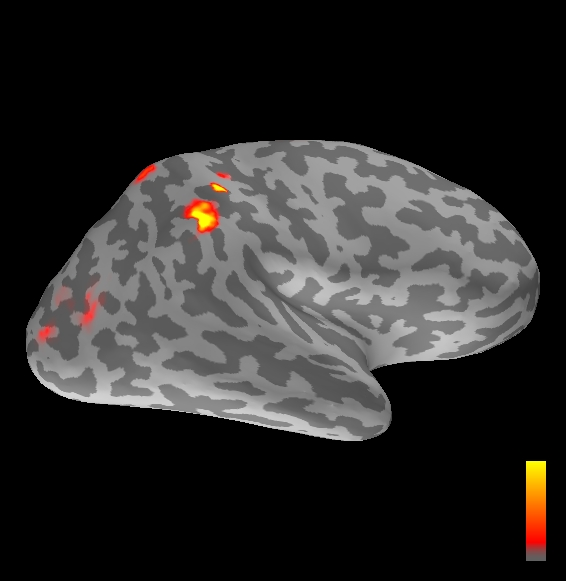

5.2 Results

We applied the ASMC sampler to MEG topographies taken from the above recordings by selecting specific time points according to the previous analysis; the parameter values in the algorithm were the same as those used for the analysis of synthetic data, with the only exception of the noise standard deviation , here estimated from the pre–stimulus interval. In order to validate the results of the ASMC, we also computed source estimates using three other methods: a PF, that approximates the posterior distribution for the current dipoles conditioned on the data up to the selected time point; dSPM, which is based on a distributed source model with an –prior, and consists in normalizing the Tikhonov regularized solution by the noise standard deviation; and sLORETA, which is similar to dSPM but is claimed to have a smaller localization bias. Figure 4 shows the results at , and ms after the stimulus onset. The results are visualized on a computer representation of the brain obtained by “inflating” the cortical surface: gray levels contain the anatomical information, light gray representing gyri and dark gray representing sulci; the activity estimate is coded in color scale, increasing from red to yellow. Importantly, this visualization allows activity in the sulci to be clearly visible; on the other hand, since neighbouring volumes may be moved apart by the inflation process, distinct activity regions are often due to underlying volumetric masses that are very close to each other.

Before describing the results, let us comment on the qualitative difference between the images produced by the ASMC sampler and the PF, on the one hand, and those produced by dSPM and sLORETA, on the other. First of all, we point out that all the quantities shown in the images of Fig. 4 are somehow related to the probability of activation at specific locations. Indeed, for both the ASMC and the PF we plot the approximation of the intensity measure (3.8); for any single grid point, this value can be interpreted as the probability of a dipole being at that location, while it integrates, over a given volume , to the mean number of dipoles within . As for dSPM, the represented quantity is a statistical value that is –distributed under the null–hypothesis of zero activity; as a direct consequence, it also yields a probability of activation, which is however not constrained to be dipolar. Similar considerations apply to sLORETA, although with a different statistical distribution. Importantly, the representation of the results is clearly affected by the setting of the visualization threshold. Owing to the explained differences between the methods, it seems reasonable to use a different value for each method. At the same time, since the plotted quantity is a probability of activation, it seems right to use the same thresholding for different time points. In this connection, the thresholds in Fig. 4 have been chosen by hand following the guidelines just outlined.

Using the same thresholding and parameters at different time points makes the four methods respond differently to the diverse intensities of the different sources. Whenever a stronger source is active, both sLORETA and dSPM will tend to produce widespread estimates, while weaker sources will be represented as small active areas. The behaviour of the ASMC and of the PF is the opposite: a stronger signal will lead to a precise localization of a dipolar source, and then to a focal marginal distribution for the location; a weaker signal will translate to higher uncertainty on the source position, and therefore a more widespread posterior map.

The phenomenon just described is indeed clearly visible in Figure 4. At ms, all the methods correctly identify the rather strong activation in the contra–lateral primary somatosensory cortex: the ASMC and the PF provide very focal maps, while dSPM and sLORETA provide compatible widespread estimates; dSPM also exhibits a more posterior peak which does not fit with the commonly agreed models of the response to median nerve stimulation; this may be due to the formerly described brain inflation.

At ms, the ASMC localizes two sources, one in the right hemisphere and a weaker one in the left hemisphere; these sources appear to be compatible, for timing and location, with the Posterior Parietal Contra and Parietal Opercular Ipsi described in Mauguiere et al. (1997). The PF finds the very same source in the right hemisphere, but it estimates no dipoles in the left one. Such discrepancy between these two methods, which are based on the same source model, is possibly due to two facts: first, thanks to its iterative nature, the ASMC is likely to explore the state space more thoroughly and is therefore more suited to identify weak sources; second, the log–uniform prior on the strength of the dipole moment in the ASMC has a wider range than the corresponding Gaussian prior in the PF. Slightly different results are provided here by dSPM and sLORETA. The activity estimate computed by dSPM seems very similar to that of ms, having the same spatial distribution with a weaker intensity. The estimate of sLORETA in the right hemisphere includes that of the ASMC and of the PF. Neither dSPM nor sLORETA find significant activity in the left hemisphere.

At ms, the ASMC localizes again two sources: a stronger one in the right primary somatosensory cortex, and a weaker one in the left posterior frontal area. Both of them seem to be compatible, for timing and location, with the results in Mauguiere et al. (1997), the left dipole corresponding to the Frontal Ipsi source. Once again, the other three methods only recover the stronger source.